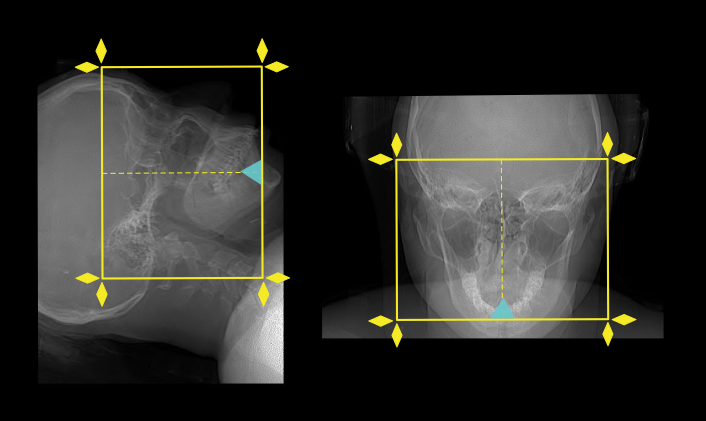

- In supine method, plan the scan slab to cover from the hard palate up to the superior border offrontal sinus.

- In prone method (neck hyperextended), plan the scan slab to cover from nose to posterior margin of sphenoid sinus. Scan slab needs to be perpendicular to hard palate, which is achieved by tilting the gantry.

- Reducing the FOV to sinus area increases image quality [7].